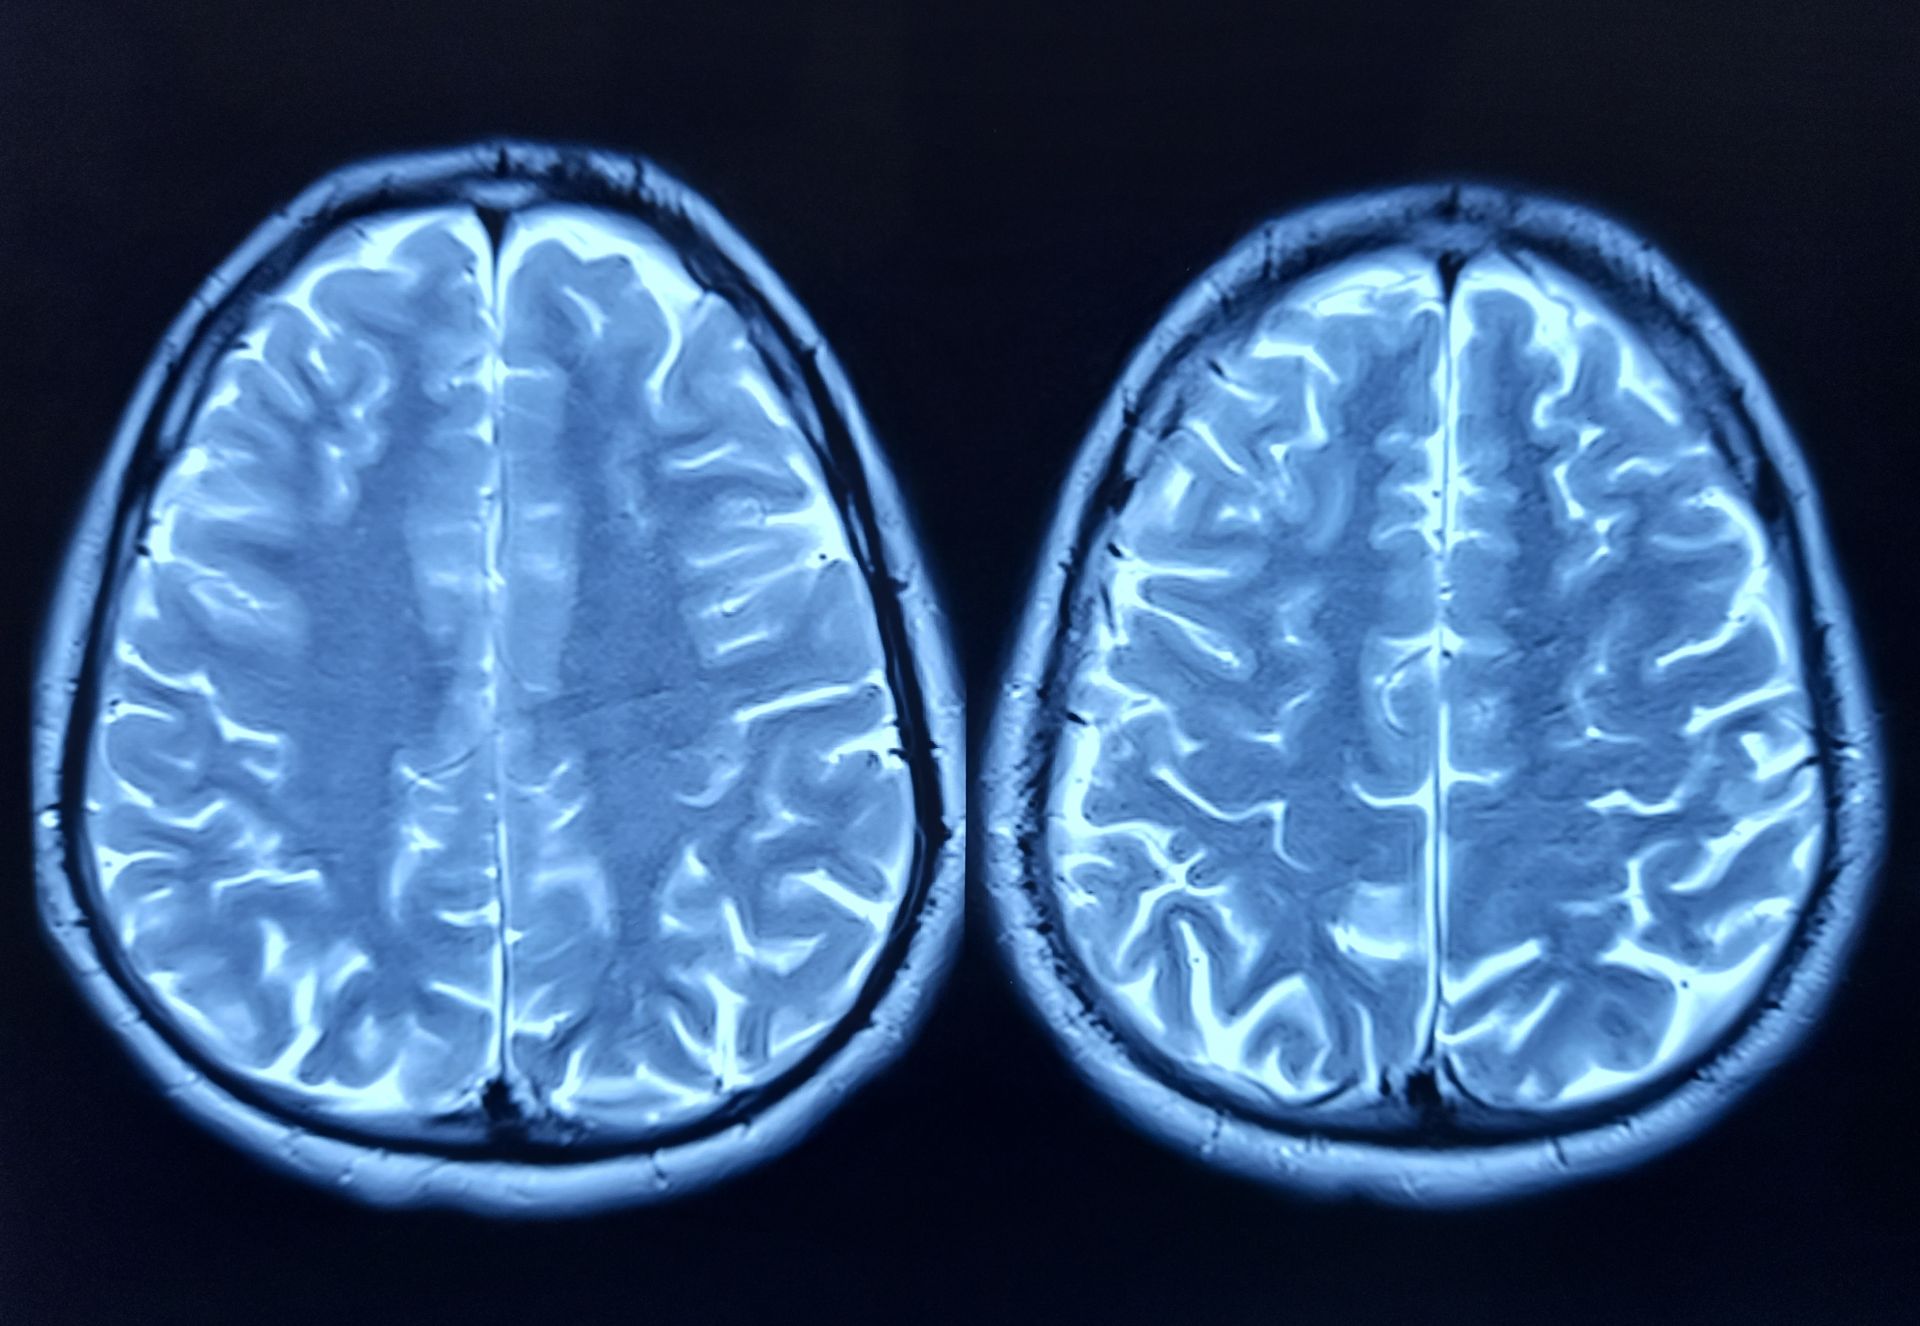

Cercetătorii au descoperit un indiciu important în lupta împotriva îmbătrânirii creierului. O proteină specifică, numită FTL1, pare să joace un rol crucial în procesul de deteriorare a memoriei și a funcțiilor cognitive. Studiile efectuate pe șoareci sugerează că nivelurile ridicate ale acestei proteine sunt asociate cu slăbirea conexiunilor dintre celulele cerebrale, un fenomen caracteristic îmbătrânirii. Îmbătrânirea are un impact semnificativ asupra hipocampului, o zonă a creierului esențială pentru învățare și memorare. Oamenii de știință au analizat evoluția genelor și a proteinelor din hipocampul șoarecilor, identificând FTL1 ca un factor cheie. Șoarecii în vârstă aveau niveluri mai mari de FTL1, mai puține conexiuni neuronale și rezultate mai slabe la testele cognitive. Cercetările au dezvăluit și o posibilă soluție. Când nivelul de FTL1 a fost redus la șoarecii bătrâni, s-a observat o îmbunătățire a conexiunilor dintre celulele cerebrale și a performanței memoriei. „Este cu adevărat o inversare a deficiențelor”, a declarat Dr. Saul Villeda, director adjunct al Institutului de Cercetare a Îmbătrânirii Bakar de la Universitatea din CALIFORNIA, SAN FRANCISCO (UCSF).

Experimentele de laborator au oferit informații detaliate despre efectele FTL1. Celulele nervoase modificate genetic pentru a produce cantități mari de FTL1 au prezentat structuri simplificate și conexiuni mai slabe. Aceste rezultate sugerează că proteina FTL1 afectează modul în care celulele cerebrale se structurează și funcționează. Studiile au arătat, de asemenea, că FTL1 influențează metabolismul celular în hipocamp. Nivelurile ridicate ale proteinei încetinesc metabolismul la șoarecii bătrâni. Totuși, cercetătorii au observat că tratarea celulelor cu un compus care stimulează metabolismul a prevenit efectele negative.